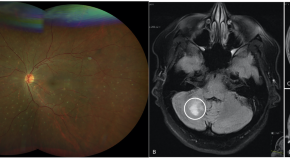

A human eye disease seems to be linked to covert mortality nodavirus, a virus commonly found in aquatic animals. The findings suggest that zoonotic transmission to humans occurs through close contact.